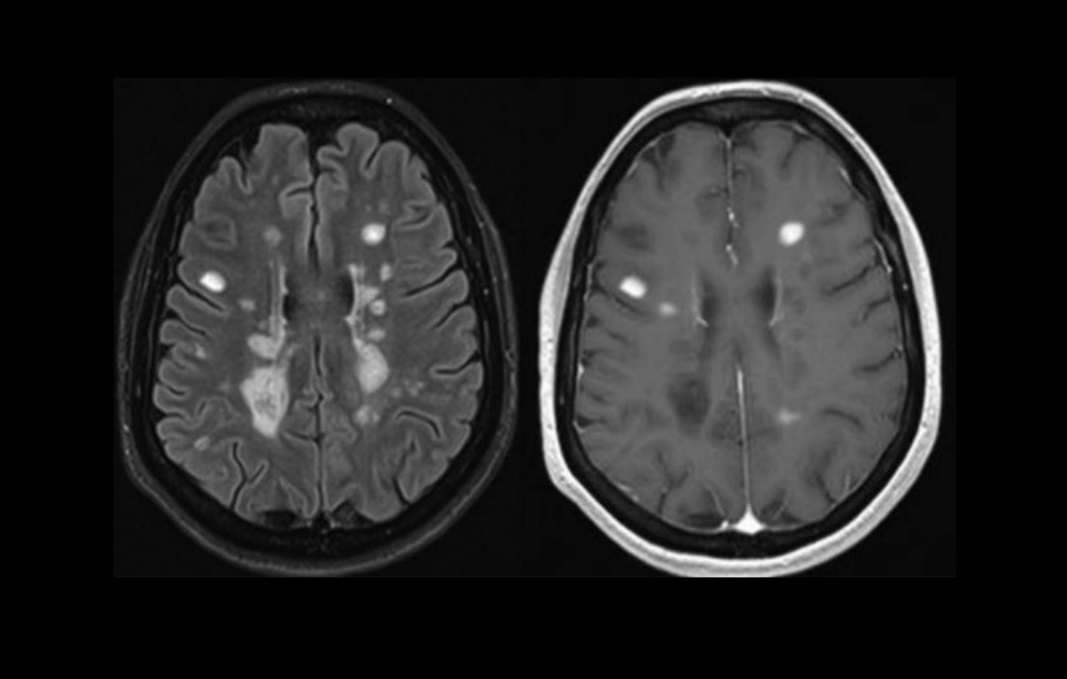

MS is a disease that causes the immune system to attack the lining of the nerves in the brain and spinal cord. The treatment—autologous haematopoietic stem cell transplant (HSCT)—works by destroying the faulty immune system using chemotherapy and is then rebuilt using stem cells harvested from the patient’s own blood.